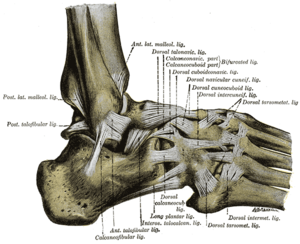

Bänder des Sprunggelenkes

Das Sprunggelenk wird durch eine Reihe von Bändern zusammengehalten. Das Deltaband (Ligamentum deltoideum oder Ligamentum collaterale mediale) besteht aus einem Schienbein-Kahnbein-Teil (Pars tibionavicularis), einem Schienbein-Fersenbein-Teil (Pars tibiocalcanea) und einem vorderen und hinteren Schienbein-Sprungbein-Teil (Pars tibiotalaris anterior und posterior). Das Außenband (Ligamentum collaterale laterale) wird vom vorderen und hinteren Sprungbein-Wadenbein-Band (Ligamentum talofibulare anterius und Ligamentum talofibulare posterius) sowie einem Fersenbein-Wadenbein-Band (Ligamentum calcaneofibulare) gebildet. Die Sprunggelenksgabel wird durch das vordere und hintere Schienbein-Wadenbein-Band (Ligamentum tibiofibulare anterius und Ligamentum tibiofibulare posterius) zusammengehalten.

Die Außenbänder sind besonders häufig von Umknickverletzungen betroffen; man spricht in diesem Fall von einer Außenbandruptur. Umknickverletzungen führen oftmals zu Schädigungen des Kapsel-Bandapparates (Bänderzerrung, -dehnung, -zerreißung). Knöcherne Verletzungen treten eher selten auf (Bruch der Außen- und Innenknöchel, Riss des Verbindungsbandes zwischen Schien- und Wadenbein). Die Sprunggelenke sind mit etwa 20 % aller Sportverletzungen sehr häufig betroffen.